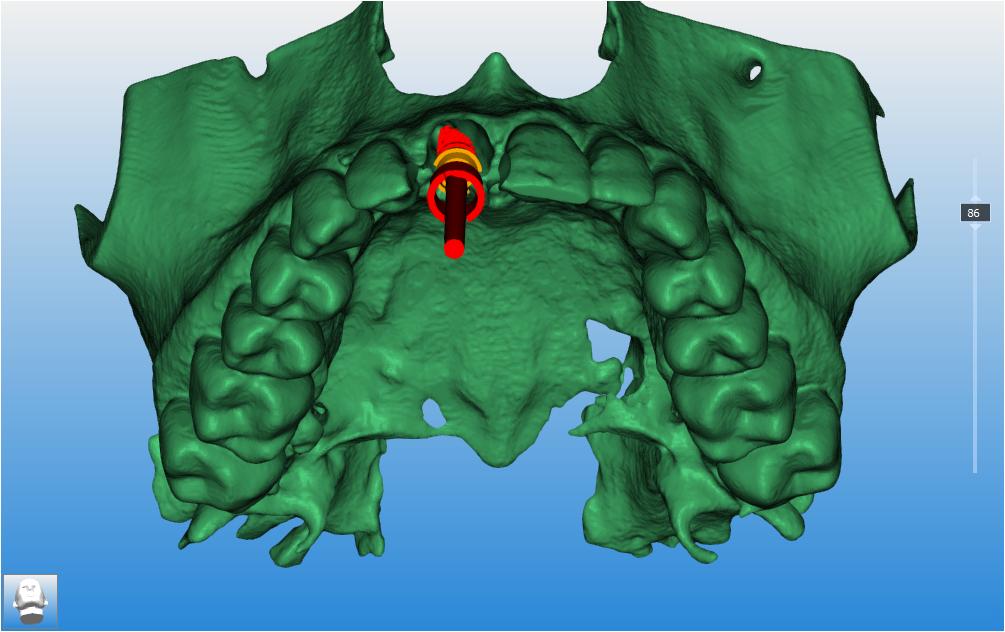

Le CBCT réalisé (fichiers dicom) est inséré dans le logiciel RealGuide pour permettre de l’associer avec

l’empreinte numérique de la patiente (Photo 8). Ces éléments nous permettent donc de simuler :

• L’avulsion de la dent 11

• L’évaluation des parois osseuses résiduelles

• La position implantaire idéale, en respectant l’axe prothétique et les contraintes anatomiques.

Un guide chirurgical a été réalisé pour guider la pose de l’implant selon la planification (Photo 9).